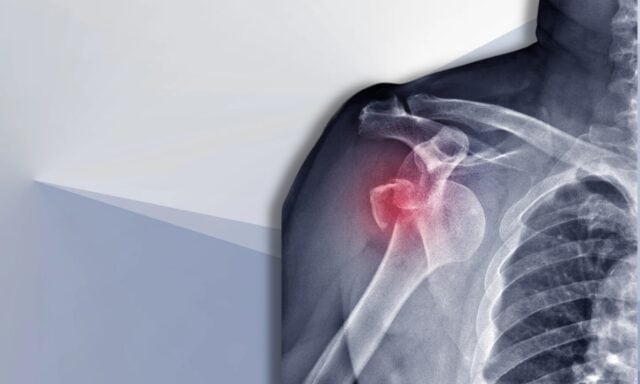

ไหล่ไม่มั่นคง

ในตอนนี้ เราจะมาพูดถึงเรื่องความไม่มั่นคงของไหล่ คุณจะได้เรียนรู้เพิ่มเติมเกี่ยวกับการจำแนกประเภท Stanmore และความเสียหายของโครงสร้างหลังจากการเคลื่อนตัว เราจะอภิปรายเกี่ยวกับผู้ป่วยทั่วไปที่มีอาการไหล่ไม่มั่นคงและขั้นตอนการตรวจจะเป็นอย่างไร เราจะพูดถึงรูปแบบการทำงานของกล้ามเนื้อ การผ่าตัด และการจัดการทางกายภาพบำบัดสำหรับผู้ป่วยที่มีภาวะไหล่ไม่มั่นคงจะเป็นอย่างไร ดังนั้นอย่าลืมฟังตอนทั้งหมด!